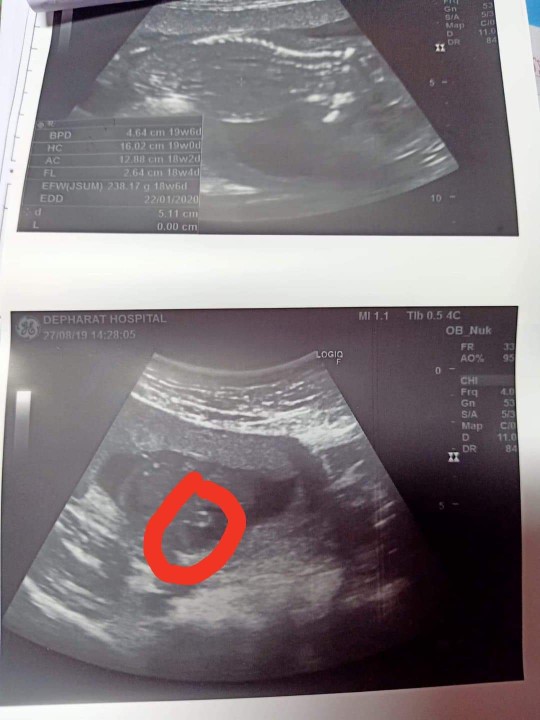

โชว์ผลซาวด์กันค่ะ

คุณลุงหมอบอกมีกลีบ?ใครมีกลีบ ใครมีแท่ง ลงมาอวดกันจร้า

ดูยังไงก็ดูไม่ออกค่ะ